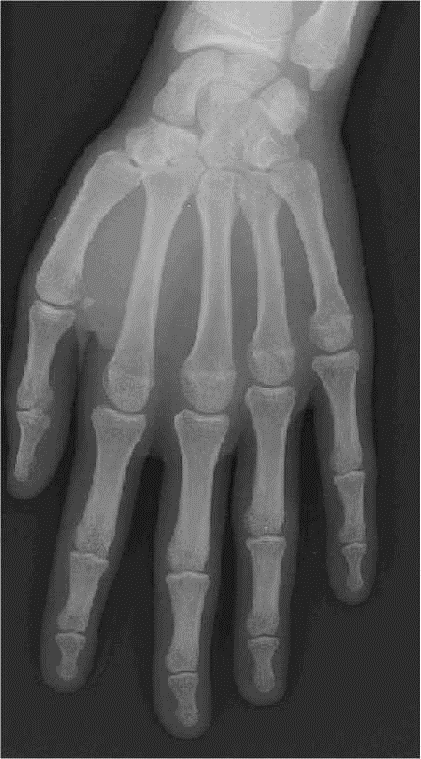

FACE

- – Patient assis parallèlement à la table (pour protéger les genoux)

- – L’avant-bras repose sur la table pomme de la main à plat sur la cassette

- – Les doigts sont légèrement écartés

Pouce en semi-abduction

RAYON DIRECTEUR

– – Centré sur la tête du 3ème méta

– – Parallèle au film

– – Sac de farine sur les dernières phalanges pour éviter de les « griller »

CRITERES DE REUSSITE

– – Voir l’ensemble de la main

– – Les méta et les phalanges doivent être bien individualisés

– – Voir les parties molles, la corticale, la médullaire.

– – Voir les interlignes métacarpo-phalangiennes et inter-phalangiennes

ANATOMIE RADIOLOGIQUE

– – Les os sésamoïdes

– – Le 2ème méta est le plus long

– – Le pouce est vue de | sur l’incidence de la main de face

IMAGE NORMALE